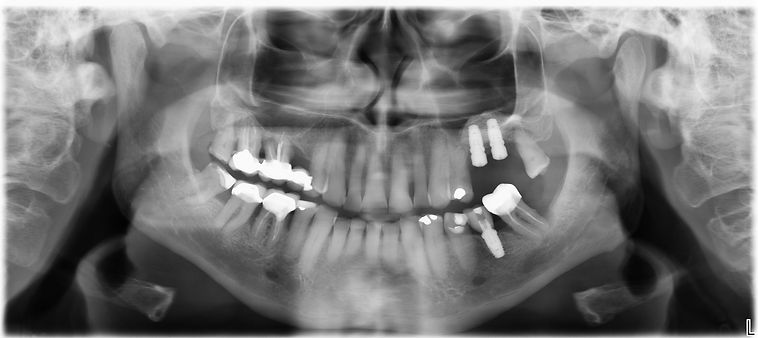

Cas clinique